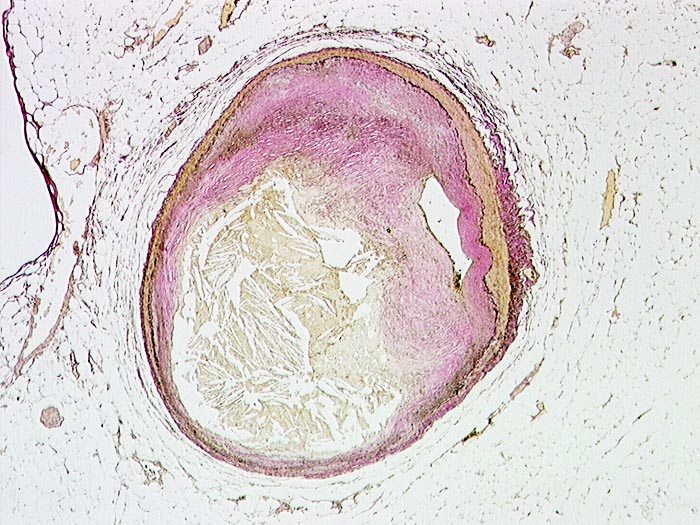

PathoPic – image database / PathoPic ID 701 - Schwer stenosierende Koronarsklerose

Schwer stenosierende Koronarsklerose

Arteria coronaris

Ein grösseres Atherom und die fibrotische Verdickung der Intima stenosieren das Lumen der Koronararterie. Es besteht eine mehr als 75 prozentige Stenose des Lumens.